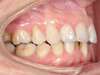

Cas N°6 : Description

Correction majeure des deux arcades dentaires liée à une mandibule rétrusive

Avant

Après